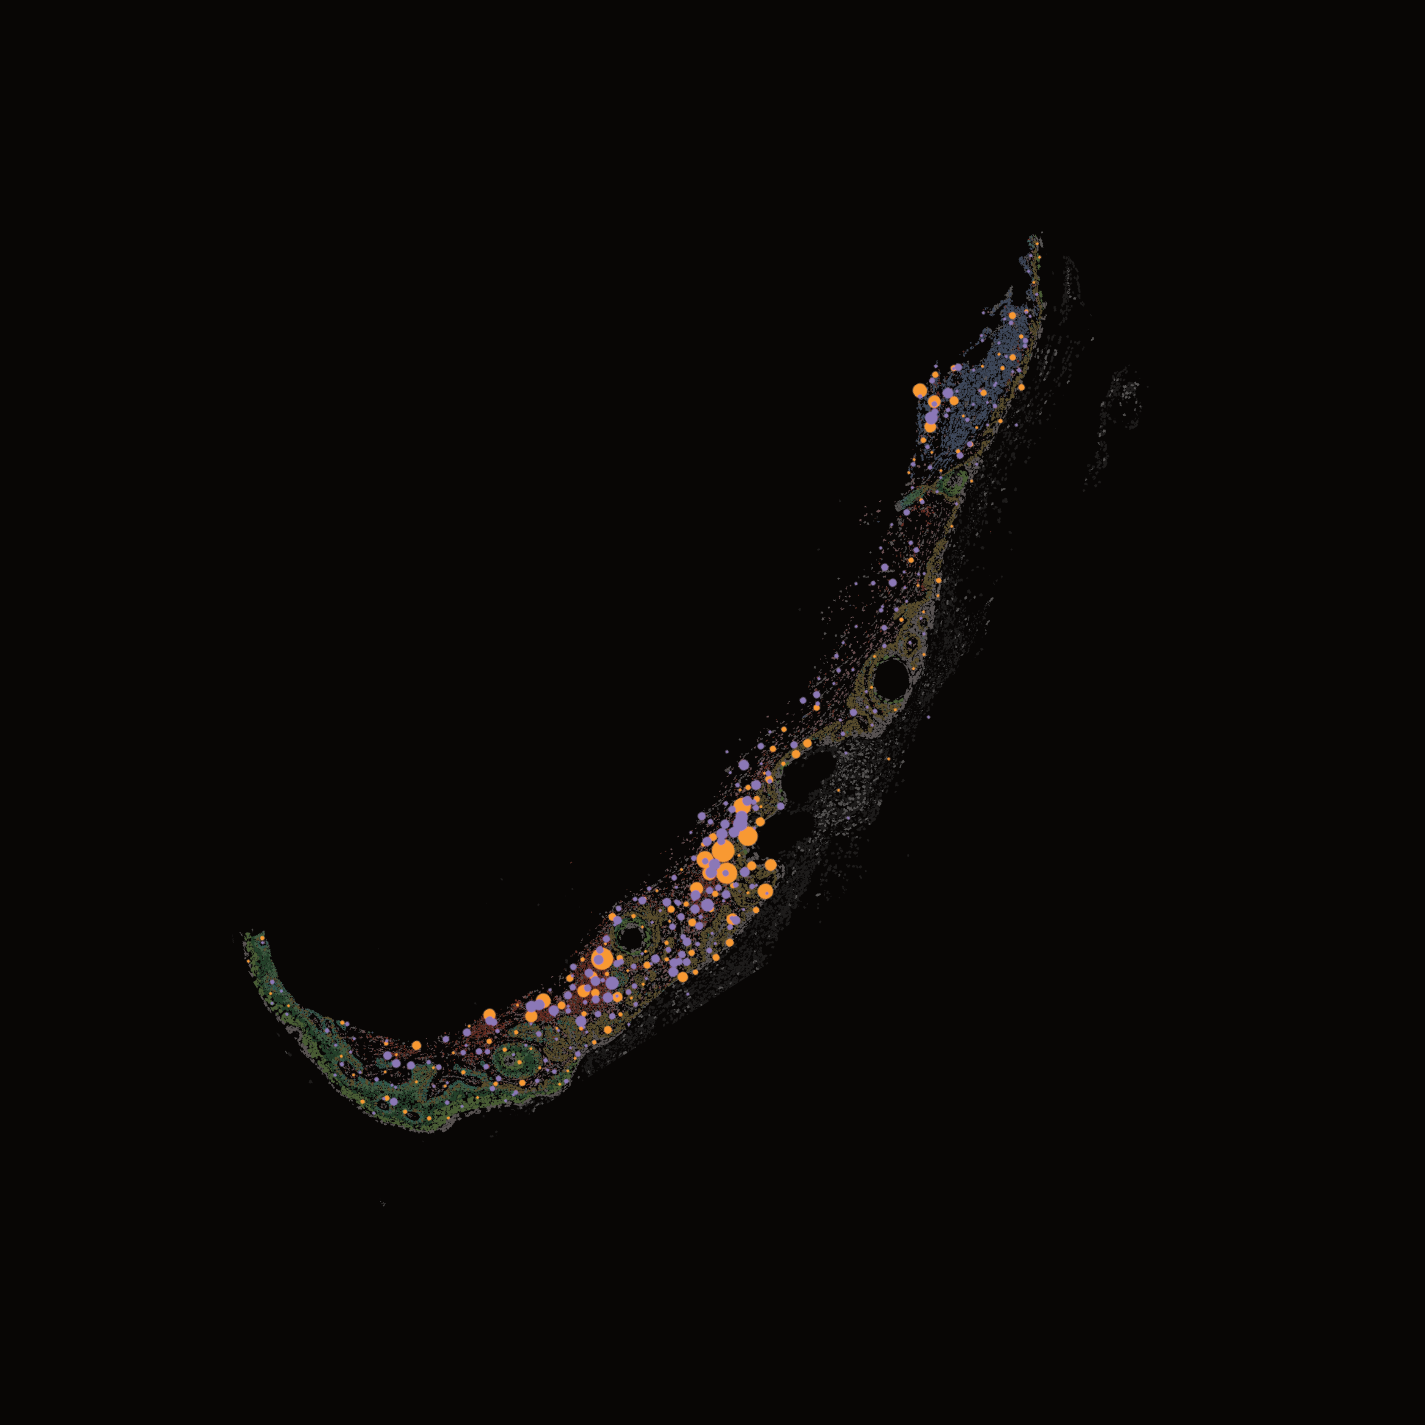

We engineer and utilize human skin equivalent organotypic systems and patient-derived samples to model skin cancer in physiologically relevant contexts. These platforms enable controlled studies of tumor growth, invasion, and microenvironmental interactions.

In particular, we leverage unique systems such as collision tumors to investigate how distinct cell populations interact and contribute to disease. By integrating these models with genomic and single-cell analyses, we gain deeper insight into the biology of rare skin cancers.